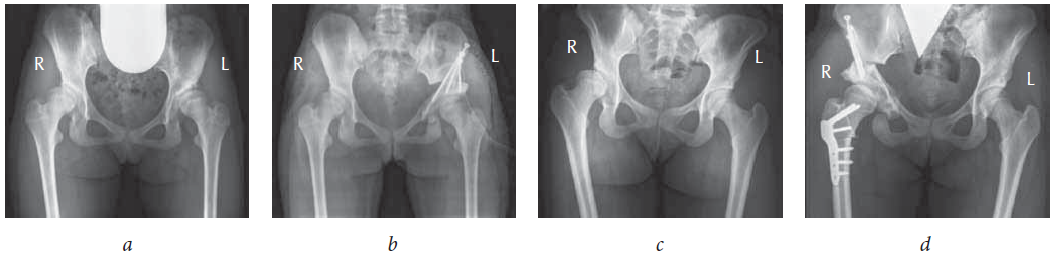

Between 2015 and 2017, we reviewed the results of surgical and regenerative treatment of 40 children (100%) with DKA at different stages. The patients comprised 27 girls (67.5%) and 13 boys (32.5%) aged 13–18 years (total 54 joints). Bilateral pathology was observed in 14 patients (35%). After a comprehensive examination, 15 patients (37.5%) were diagnosed with DKA stage I, 15 (37.5%) with stage IIa, and 10 (25%) with stage IIb. An informed consent was obtained from all patients to participate in the study, to process personal data, to examine and perform surgical intervention. All 40 patients (100%) underwent transposition of the cotyloid cavity after triple osteotomy of the pelvis, alone or in combination with femur osteotomy (Fig. 1). Of note, surgery was performed based on a technique developed in the Department of Hip Joint Pathology (Turner Scientific and Research Institute for Children’s Orthopedics, Saint Petersburg, Russia) from the external-lateral access. In addition, clinical, radial, and electrophysiological research methods were used to assess the anatomical and functional state of the affected hip joint. The clinical examination comprised goniometry, limb length measurement, and gait evaluation. Radiation methods facilitated complex X-ray assessments based on the commonly used indicators (e.g., the angles of Wiberg and Sharp, front cover, inclination of the cavity in the sagittal plane and cervical–diaphyseal and that of the antetorsion, thickness of the cavity bottom, lateral and cranial displacement of the femoral head, and coefficient of the bone coverage) and assessed the severity and dynamics of DDC. In EMNG and EMG studies, the state of the nervous and muscular systems was determined before surgery, followed by evaluation and analysis of the data obtained. In the ENMG study of the femoral, tibial, and peroneal nerves, nerve conductivity was assessed from both sides, including the state of myoneural apparatus of the lower extremities and the dependence of the severity of the deviation of neurophysiological indices of the normal ones. For a comprehensive assessment of the functional condition of the hip joint, all patients were asked to complete the questionnaire of the modified Harris Hip Score scale, signifying the functional condition of the hip joint, and that of the scale developed at the Turner Scientific and Research Institute for Children’s Orthopedics, which characterizes the violations in the typical life of adolescents to a greater extent. The data obtained during this study were processed using the Statistica for Windows (version 6.0) program.

Fig. 1. Radiography of the hip joints in direct projection of patients in the treatment and control groups: a — Patient K., 14 years old, diagnosed with bilateral DKA of stage II, before surgery radiograph; b — Patient K., 14 years old, after transposition of the cotyloid cavity following triple osteotomy of the pelvis on the left. Osteosynthesis of fragments with malleolar screws is seen; c — Patient S., 17 years old, diagnosed with right-sided DKA stage IIa, before surgery; d — patient S., 17 years old, after transposition of the cotyloid cavity following triple osteotomy in combination with corrective osteotomy of the right femur. Osteosynthesis of pelvic fragments with malleolar screws and femur with a plate with angular stability (LCP pediatric hip plate) is seen